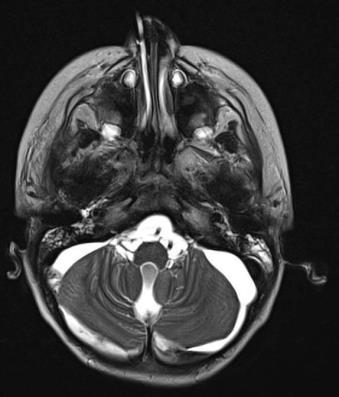

Brain and Spinal Cord MRI:

- Cranio-spinal trauma;

- Probable dissection of the right internal carotid artery;

- Aneurysm with subarachnoid and ventricular hemorrhage.

CT Scan of the Brain, Facial Mass, and Spine:

- Multiple fractures of the skull base and cranial vault;

- No vertebral fractures (no spinal cord compression);

- Displaced fracture of the mandibular condyle and right orbital floor;